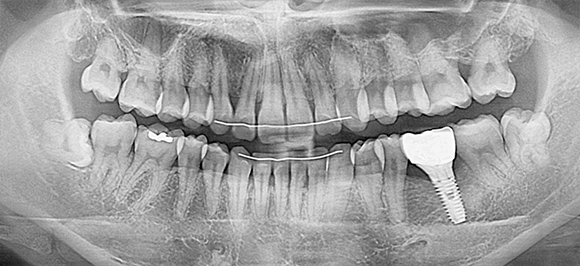

임플란트 재수술

상악동과 더불어 치과치료 중 난이도가 높은 임플란트

기존 임플란트가 빠지거나 흔들린다면 이를 제거하고 인공치근을 재식립

재수술이기 때문에 악화된 상태에 따라 그만큼 견고한 치료가 요구